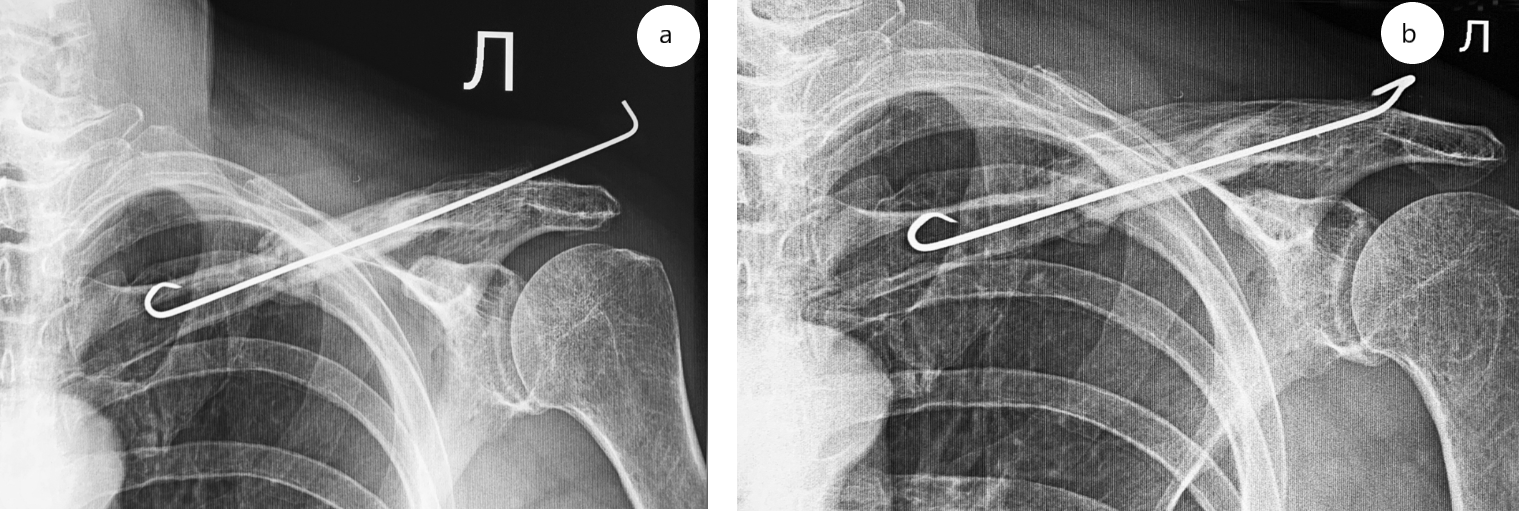

Пациент 70 лет в марте 2018 г. в результате падения получил перелом средней трети диафиза левой ключицы. В течение четырех месяцев он проходил консервативное лечение в амбулаторных условиях, закончившееся формированием несращения (рис. 1 а).

В одном из стационаров города был выполнен накостный остеосинтез левой ключицы пластиной АО 1/3 трубки с угловой стабильностью в сочетании со серкляжным швом (рис. 1 b).

Рис. 1. Рентгенограмма ключицы пациента: а — при поступлении;b — после накостного остеосинтеза